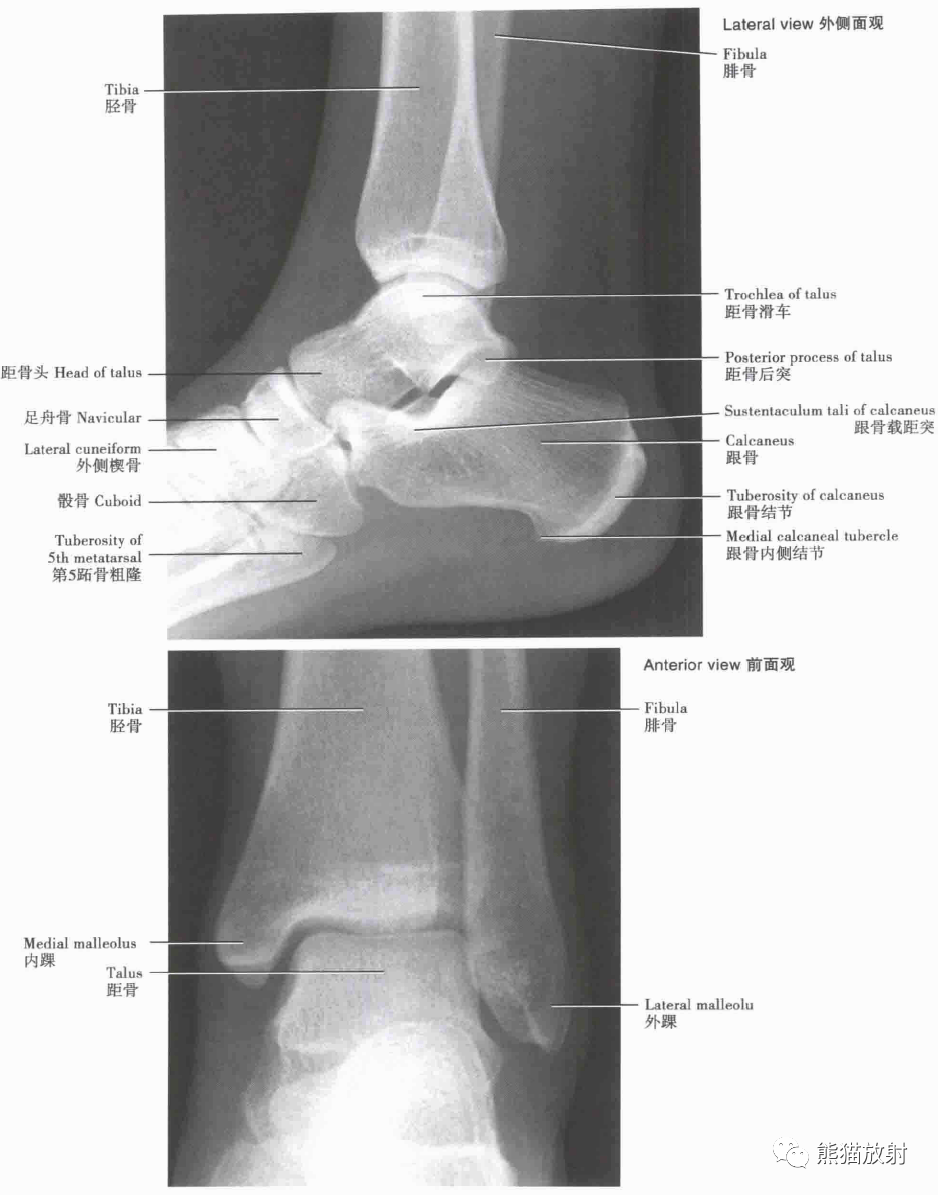

完美33张踝关节解剖高清图解

超清晰的下肢小腿踝与足解剖图

跟骨-x线片-解剖图片